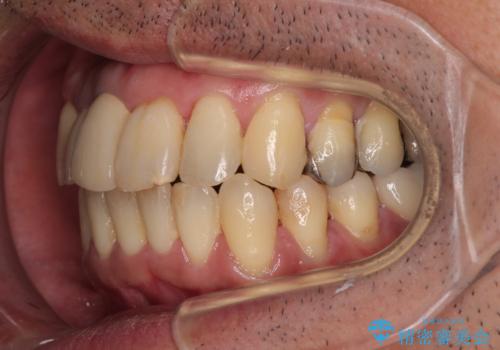

隠れている前歯 インビザライン矯正治療と前歯のセラミック治療

- 隠れるほどに内側に転位しいてる前歯を気にして来院された患者様です。

仕事柄海外出張が多いとのことで、インビザラインにて矯正治療を行うこととしました。

矯正治療後は、前歯や下顎の奥歯など、むし歯治療途中の歯をオールセラミッククラウンにて補綴治療を行うこととしました。

内側に転位していた前歯は、矯正治療では治しきることができませんでしたが、幸いにもオールセラミッククラウンに置き換える予定であったため、希望通りの仕上がりとなりました。